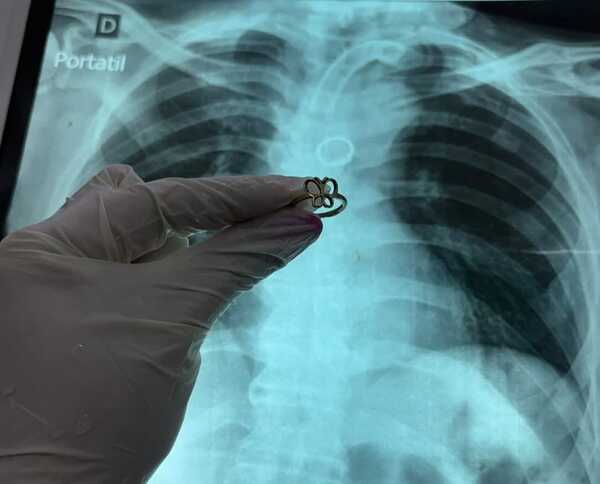

Popular / Extraen anillo de oro del pulmón de un karai traqueostomizado

¡Jeyma! Médicos del Instituto de Enfermedades Respiratorias y del Ambiente (Ineram) extrajeron del pulmón izquierdo un anillo de oro; de un paciente traqueosteomizado de 54 años. El karai inmovilizado oho al nosocomio para realizarse estudios de rutina y grande fue la sorpresa de los galenos; cuando mediante una radiografía pillaron que orekóma un […] ...[Leer más]